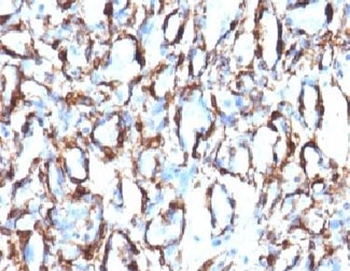

IHC: Formalin-fixed, paraffin-embedded Leiomyosarcoma stained with Smooth Muscle Actin antibody (clone SPM332).